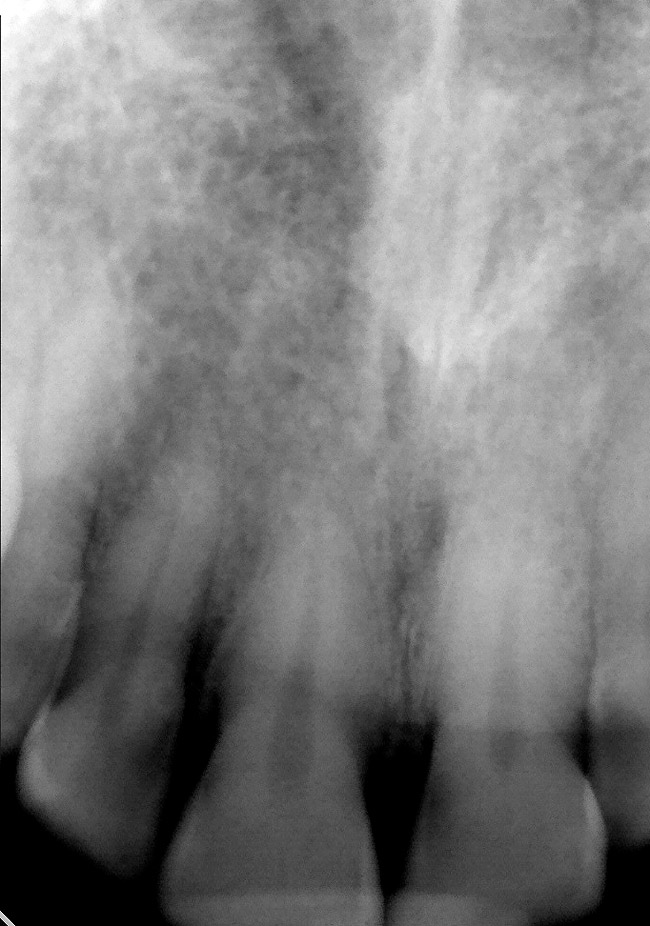

Figure 6B Periapical radiograph. Deep caries evident radiographically for the mandibular first molar.

Figure 6B

Figure 7A Deep caries evident on the radiograph for tooth No. 9.

Figure 7A